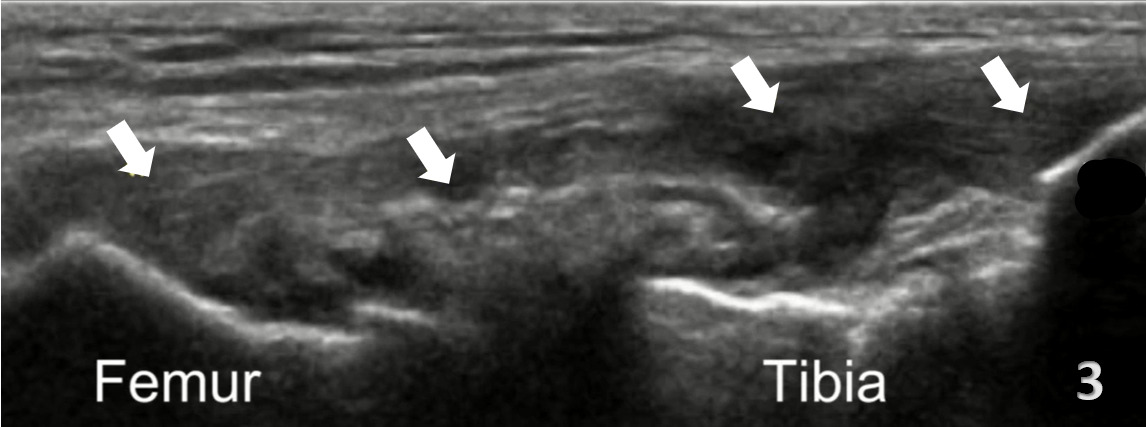

In the LAX view, depending on the probe width and size, one should start distally to visualize the hyperechoic reflection of the bony cortex of the fibular head distally and the cortex of the femoral epicondyle more proximally. If the depth is increased enough, you will also be able to visualize the bony reflection of the tibia directly below the fibular head. Usually, the LCL demonstrates a hyperechoic fibrillar pattern. The distal portion of the tendon may appear heterogeneous and thickened due to the bifurcating distal biceps femoris tendon that runs both superficial and deep to the LCL.9

Disruption of fibrillar pattern of the ligament in partial tears and ruptures.

Associated joint effusion, presenting as anechoic regions.